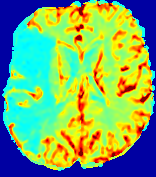

LesionRefer to captionRefer to captionRefer to captionRefer to captionRefer to captionRefer to caption𝐕rgbsubscript𝐕𝑟𝑔𝑏{\bf{V}}_{rgb}Refer to captionRefer to captionRefer to captionRefer to captionRefer to captionRefer to caption𝐕2subscriptnorm𝐕2{\|\bf{V}}\|_{2}Refer to captionRefer to captionRefer to captionRefer to captionRefer to captionRefer to captionRefer to caption3.53.53.52.82.82.82.12.12.11.41.41.40.70.70.70.00.00.0(mm/s)𝑚𝑚𝑠(mm/s)D𝐷DRefer to captionRefer to captionRefer to captionRefer to captionRefer to captionRefer to captionRefer to caption0.0200.0200.0200.0160.0160.0160.0120.0120.0120.0080.0080.0080.0040.0040.0040.0000.0000.000(mm2/s)𝑚superscript𝑚2𝑠(mm^{2}/s)Slice #1Slice #2Slice #3Slice #4Slice #5Slice #6

Figure 3: PIANO feature maps for one stroke patient, where the lesion is located in the left hemisphere. Top row: segmented stroke lesion region (white) on different slices, obtained from ISLES 2017. The corresponding slices for the PIANO feature maps are shown in the following rows.

For a better insight into an estimated velocity field 𝐕𝐕{\bf{V}} and diffusion field 𝐃𝐃{\bf{D}}, we compute the following maps: (1) 𝐕rgbsubscript𝐕𝑟𝑔𝑏{\bf{V}}_{rgb}: Color-coded orientation map of 𝐕=(Vx,Vy,Vz)T𝐕superscriptsuperscript𝑉𝑥superscript𝑉𝑦superscript𝑉𝑧𝑇{\bf{V}}=(V^{x},V^{y},V^{z})^{T}, obtained by normalizing 𝐕𝐕{\bf{V}} to unit length and mapping its 3 components to red, green, blue respectively; (2) 𝐕2subscriptnorm𝐕2\|{\bf{V}}\|_{2}: 222 norm of 𝐕𝐕{\bf{V}}; (3) D𝐷D: scalar field in Eq. 5.

Fig. 3 and Fig. 4 show the PIANO feature maps estimated from two ISLES 2017 patients: all are highly consistent with the lesion in both cases. Details of the blood flow trajectories are revealed in 𝐕rgbsubscript𝐕𝑟𝑔𝑏{\bf{V}}_{rgb} by the ridged patterns and the sharp changes of colors in the unaffected (right) hemisphere, while the flat patterns appearing within the lesion provide little directional information about the velocity and indicate low velocity magnitudes. Velocity magnitudes are more directly visualized via 𝐕2subscriptnorm𝐕2\|{\bf{V}}\|_{2}, from which one can easily locate the lesion where 𝐕2subscriptnorm𝐕2\|{\bf{V}}\|_{2} is low. D𝐷D also indicates lower diffusion values in the lesion, though with less contrast potentially due to the fact that it captures the accumulated effect of CA diffusion at the voxel-level.